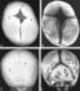

Metopic craniosynostosis

Craniosynostosis is a condition in which one or more of the fibrous sutures in an infant (very young) skull prematurely fuses by turning into bone (ossification), thereby changing the growth pattern of the skull. Because the skull cannot expand perpendicular to the fused suture, it compensates by growing more in the direction parallel to the closed sutures. [Source: Wikipedia ]